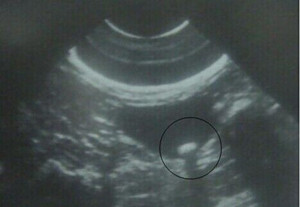

1、检查费用:治疗结石之前对于病情的检查是很必要的,一般包括放射学检查、超声波检查等,以此来确定结石的大小、位置、数量、胆囊功能损伤程度等。这部分的费用是不可以省去的。